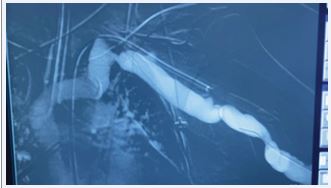

A female patient, 48 years, with a previous history of two unsuccessful kidney transplants, with a basilic vein transposition (brachial-basilic) arteriovenous fistula and a Viabahn 8x100 implanted at brachial artery due to an aneurysm, was admitted at the emergency room with an important AVF bleeding. The patient was admitted with a cut and bruise wound left arm (bathroom stall), which evolved into a basilic vein laceration and acute hemorrhagic shock. Due to the important bleeding, an arm tourniquet was applied, which provoked an AVF and brachial artery acute thrombosis. The patient was urgently submitted to an endovascular treatment of the AVF and brachial artery acute thrombosis. Under general anesthesia, a left common femoral artery was retrograde punctured guided with a duplex ultrasound to perform the whole intervention percutaneously with a proper sheat. Then, upper left arm arteriography showed: brachial artery occlusion immediately before stenting, with brachial artery refilling before anastomosis focal venous stenoses. (Figures 1 and 2).

Figure 1 Intraoperative image showing brachial-basilic arteriovenous fistula and a Viabahn occlusion.